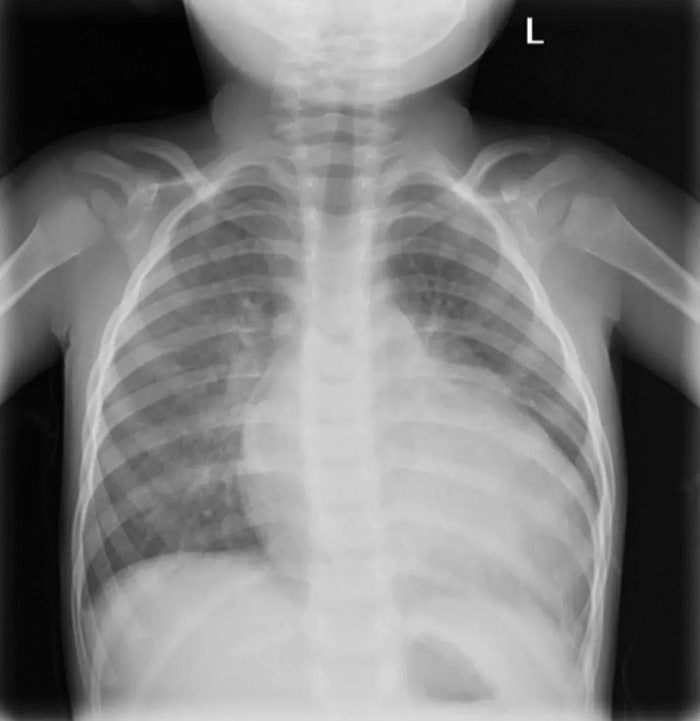

© Ο Δρ Chris Flowers, MD, με τη βοήθεια του Midjourney και του Photoshop